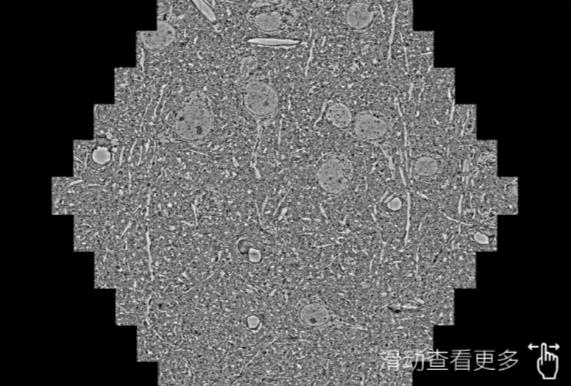

鼠脑切片。左图使用大连蔡司大连扫描电镜MultiSEM706对165μmx143pm面积区域成像,耗时仅需1.5秒。右图为鼠脑切片中30μm区域放大效果。样品由芝加哥大学B.Kasthuri提供。

使用蔡司高速大连扫描电镜MultiSEM对1mm²人脑皮层组织进行高分辨成像,并对其中的各种细胞结构进行三维重构分析。左图展示了2x3mm²组织平面中锥体神经元的三维重构效果。右图显示了局部体积神经元三维重构。图像由哈佛大学chtman实验室提供,渲染图由D. Berger 制作。